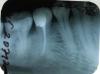

charity Опубликовано 2 июля, 2012 Поделиться Опубликовано 2 июля, 2012 На днях припухла десна около 45,46 зубов, 45 зуб был пролечен в октябре 2011 года, канал запломбирован, 46 - в январе 2012 лечили с диагнозом глубокий кариес. Боюсь как бы не периодонтит опять. 7 июля уезжать в отпуск. Посмотрите, пожалуйста, снимок и подскажите, насколько все серьезно и стоит ли срочно обратиться к врачу или ситуация может пару недель подождать? При надавливании или жевании боли нет, при постукивании 45го ощущения слегка болезненные. Ссылка на комментарий

diesel87 Опубликовано 3 июля, 2012 Поделиться Опубликовано 3 июля, 2012 По снимку, на хронический гранулематозный периодонтит; в клинике, еще и на его обострение, раз появился отек и болезненная перкуссия. На десне со стороны щеки, выбухание есть какое нибудь (свищ)? Ссылка на комментарий

charity Опубликовано 3 июля, 2012 Автор Поделиться Опубликовано 3 июля, 2012 со стороны щеки вообще никакой припухлости нет. только со стороны языка. свища нет. Сходила все-таки в клинику на консультацию. Так там вообще сказали, что на снимке видны всего лишь остаточные явления воспалительного процесса, от которого и был в прошлом октябре пролечен зуб, а десна припухла от воспаления межзубного кармашка. посоветовали полоскать корой дуба и мазать метрагилом-дента. Ссылка на комментарий

IvanK Опубликовано 3 июля, 2012 Поделиться Опубликовано 3 июля, 2012 Явления периодонтита на снимке есть..Контакт между зубками плотный? Или нитка как "карандаш в стакане"? Очень много всяких нюансов... сходите на консультацию. А то у нас: "Ремонтирую машины по фотографии.." Ссылка на комментарий